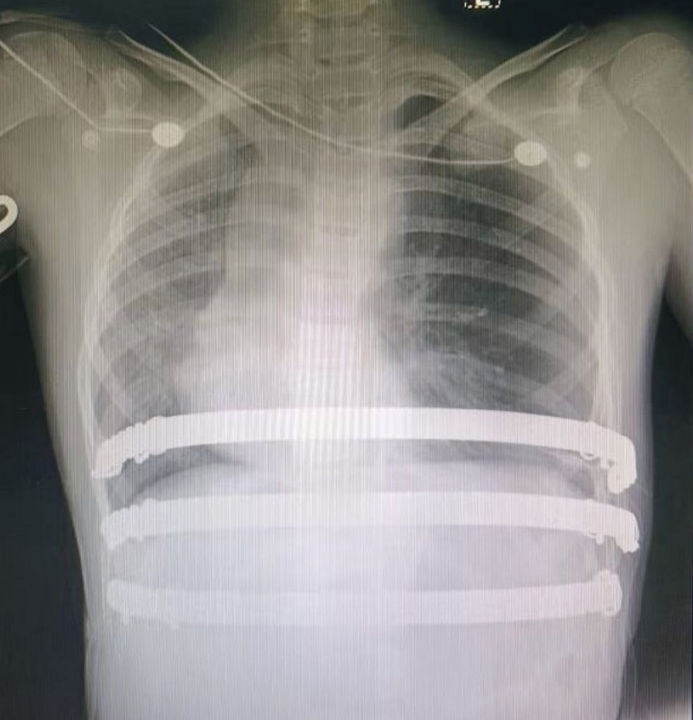

The anterior chest wall shows a severe asymmetric depression, causing marked compression of the heart, which is displaced toward the right thoracic cavity. The patient also presents with scoliosis. She is diagnosed with malignant pectus excavatum.

In clinical practice, when a depression develops in the chest wall and exerts pressure on the heart, the heart is more likely to be displaced to the left due to its normal anatomical position. Rightward displacement of the heart is extremely rare and, when present, often indicates significant cardiac compromise, putting the patient at high risk of developing serious symptoms. Based on these considerations, the chest wall deformity in this case was classified as malignant pectus excavatum, necessitating prompt surgical intervention.